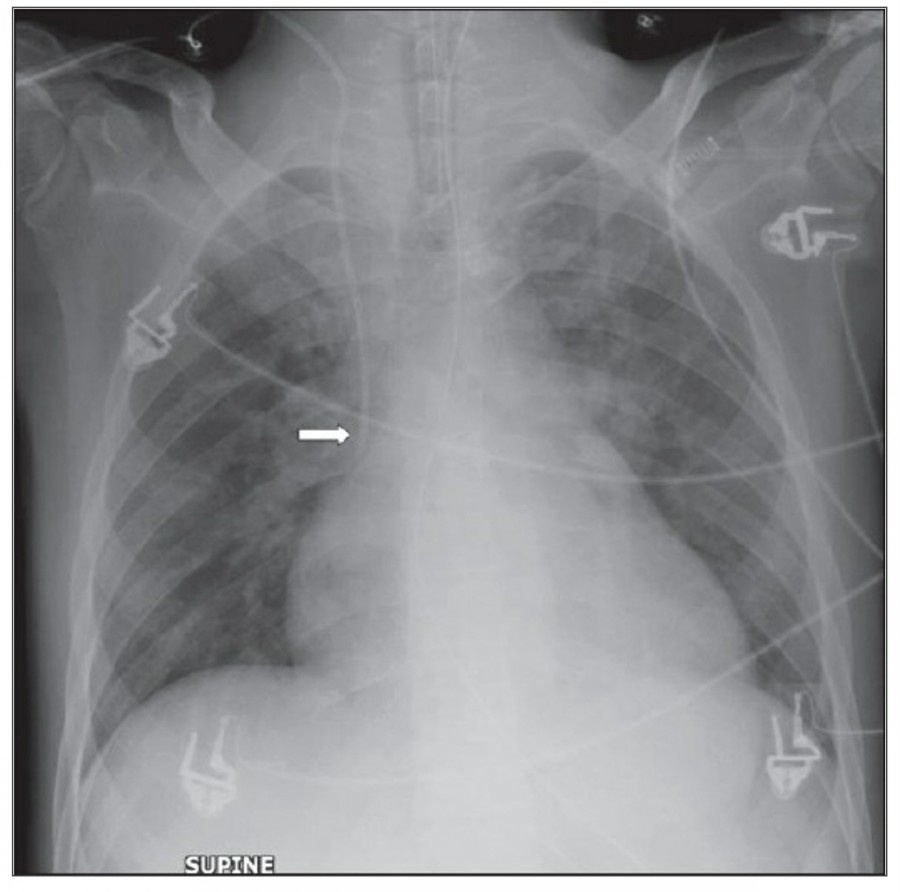

중환자에서 pneumothorax의 진단은 종종 supine radiograph에서 내릴 수 있다. Supine position에서 공기는 anteromedial 방향으로 모이게 되는데, apical air collection이 있을 경우 large pneumothorax가 있음을 시사한다. 공기는 lung과 diaphragm 사이의 subpulmonic location에 trap 되어 있을 수도 있다. 공기가 costophrenic sulcus로 anterolateral extension 될 경우, 이 costophrenic sulcus의 radiolucency를 증가시키는데, 이를 deep sulcus sign이라고 한다. Subpulmonic pneumothorax의 다른 특징으로 diaphragm의 superior surface와 IVC 윗부분이 뚜렷하게 보일 수 있다.

중환자에서 tension pneumothorax의 진단은 매우 힘들다. ARDS와 같은 lung의 병리적인 기전이 lung compliance를 감소시킴으로써 total lumg collapse를 막는다. 또한 tension pneumothorax의 특징인 mediastinal shift가 PEEP으로 인해 나타나지 않을 수 있다. Chest X ray 상에서 tension pneumothorax는 hemidiaphragm의 depression이나 heart border, SVC, IVC의 이동으로 나타날 수 있다.

Pleural effusion

방사선 소견상 Pleural effusion은 환자 흉부의 dependent area에 고인다. Erect position에서 확인하기가 쉬운데, 폐의 base에 고임으로써 costophrenic angle blunting을 보이고 lower lobe vessel들의 흐리게 한다. Supine position에서는 확인이 더 어려운데, pleural fluid는 posterior basilar space에 고여서 폐 base 쪽으로 intensity가 증가하는 homogenous density를 보인다. 정상적인 bronchoalveolar marking은 이와 같은 veil-like density 안에서 확인 가능하다. Fluid 양이 늘어나면서 diaphragm의 윤곽이 흐릿해지고 costophrenic angle도 없어지는데, 이 costophrenic angle blunting이 없더라도 pleural space에 1L 정도의 pleural fluid가 있을 수 있다는 것을 기억해야 한다. 그 양이 더욱 늘어날 수록 fluid는 lung의 apex에서 pleural cap으로 나타날 수 있으며, 이는 supine position에서도 확인 가능하다. Pleural fluid는 lung의 medial side에 고일 수도 있으며 이는 mediastinum의 확장으로 보일 수도 있다.